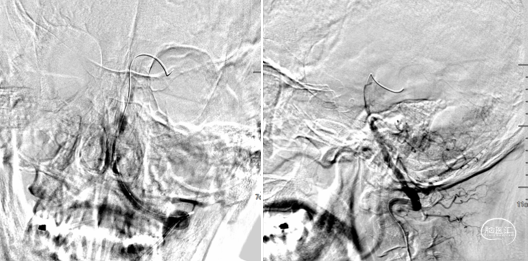

2.5*15mm球囊6atm 压力。

球扩后造影,远端大负荷量血栓,抽吸效果更佳,且患者局麻操作,越快越好,操作越复杂风险越大,故更换器械。

AXS Infinity导管鞘结合AXS Catalyst 7颅内支持导管,导管鞘支撑裸奔到位,抽吸10s后明显落空,大量血栓。

AXS Infinity LS导管鞘结合AXS Catalyst 7颅内支持导管。导管鞘支撑,颅内支持导管送至基底动脉远端再次抽吸,多次抽吸无负压后结束抽吸 。

抽吸再通后造影,近端残余明显狭窄且局部毛糙,拟支架成型。

3.0*8 mm球扩支架,小压力,减少穿支损伤。

支架后造影

最后造影